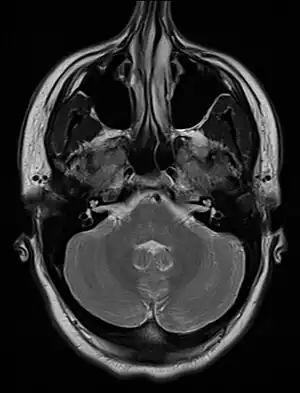

| An MRI image showing a congenitally deviated nasal septum | |